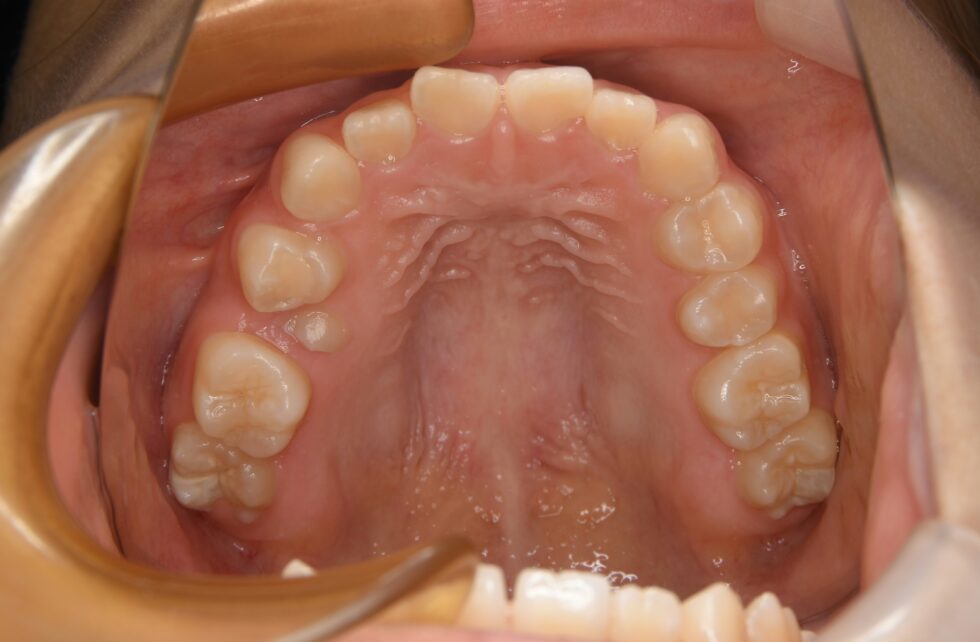

初診時年齢14歳の女子 上顎右側第二小臼歯の埋伏を主訴に遠方の歯科医院より紹介来院した。

埋伏している小臼歯は歯冠を遠心に向けて埋伏しており口蓋側面が歯肉から少し露出していた。また、歯列内に移動するための余地も5㎜程度不足しており、この余地を作ることと、埋伏歯の牽引を同時に行うことを目標に治療を開始した。近心を向いていた歯根の移動に時間を要し、頬舌側を逆転する形で歯列内に配列した。従って、頬側側にある口蓋側咬頭の咬合状態は甘いが、口蓋側にある頬側咬頭は咬合接触を得ることができた。動的治療3年3か月間で保定へ移行した。